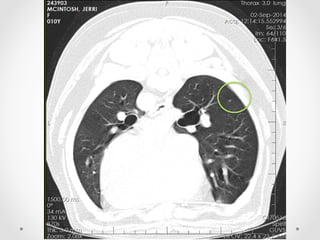

• 12.

Diagnostic imaging dx: Largeaggressive soft tissue lesion with invasion and destruction of proximal left ulna - likely neoplastic. CT  forelimbs  (bone  &  soft  tissue  windows)

Considerations •  Tried simulatinga left forelimb amputation by bandaging it up •  The worrying CT scan findings o  Pulmonary metastases – prognosis slightly poorer (though early stage metastatic disease as not detected on radiography yet) o  Compromised right elbow – arthritic change + possible neoplasm as well